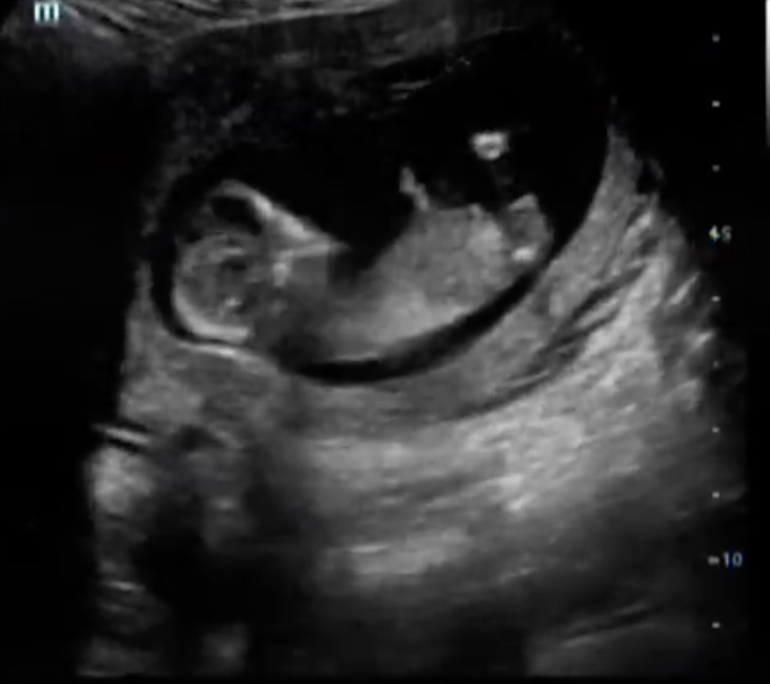

Эксперты по бугоркам - ау :)

Были сегодня на скрининге с крохой, врач на 65 процентов предположил пол :) Скоро будет НИПТ, проверим :)

Как вы думаете, мальчик или девочка? (фото подкат)

Бугорок ну прям сразу же видно , что девчачий , мальчика тут , нуу никак нельзя было увидеть.

Девочка. У моего мальчика бугорок под углом 90° торчал, здесь параллельно позвоночнику.